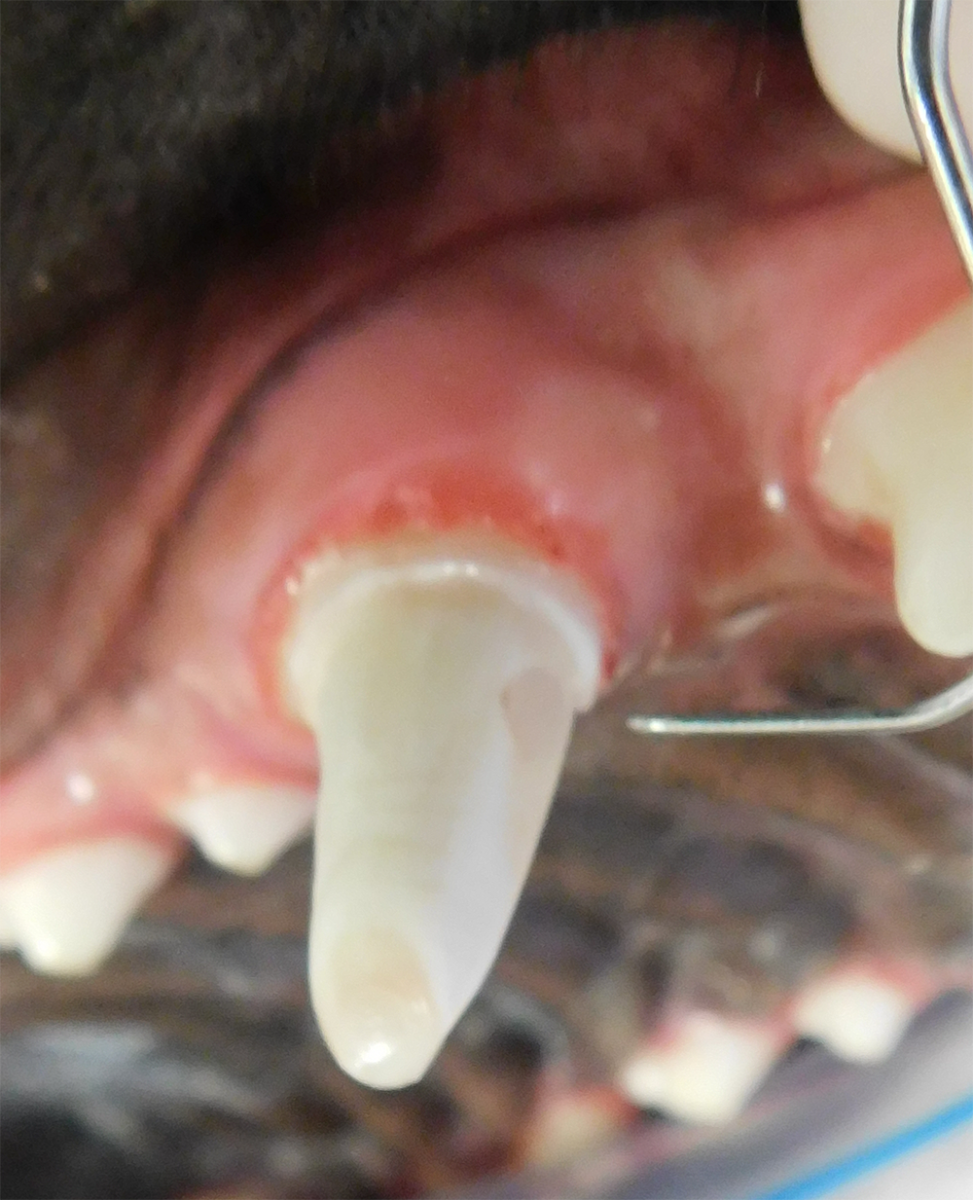

Tooth resorption is a disease process where the body begins to break down the adult tooth. It is widely known to occur in cats but can also occur in dogs. In cats these lesions are thought to be inflammatory, while in dogs they can be more of a replacement resorption process. These lesions can be very painful and should be treated, generally with extraction depending on the type of resorption that is occurring. The disease can be progressive and affect many teeth over several years. It is important to have regular checkups and yearly dental cleanings to monitor for these lesions.

Periodontal disease is extremely common in dogs and cats. Over 80% of dogs and cats over two years of age have some degree of periodontal disease. Periodontal disease is best prevented by yearly professional dental cleanings starting at two years of age and at home brushing at least three times weekly. Brushing should begin at a very early age to allow your new pet to get used to regular brushing. In severe cases of infection or periodontal disease, the teeth may need to be surgically extracted. Extractions should always involve x-rays of the tooth first, as many teeth have multiple roots or may be diseased below where the eye can see. Extracting larger teeth in animals requires oral surgery, equivalent to removing wisdom teeth in people. It is vital that all of the tooth and roots be removed for the periodontal infection to resolve. In cases of important teeth with mild to moderate periodontal disease, multiple periodontal treatments can be offered to help save these teeth.